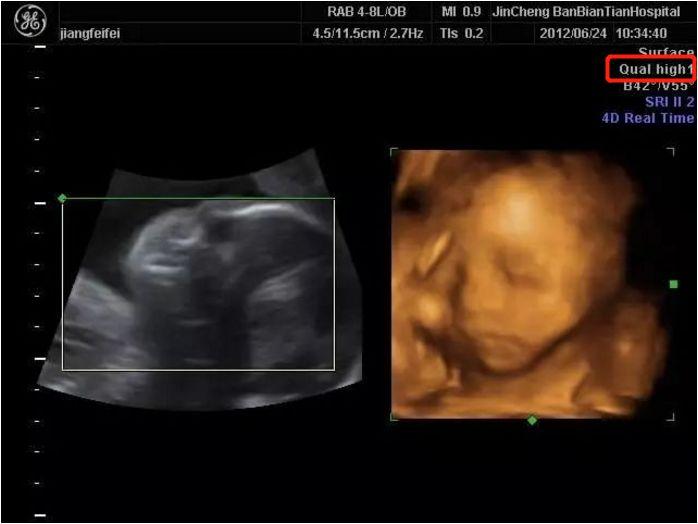

妊娠16週5日(16w5d)で性別がわかった! 妊娠16週5日(16w5d)のエコー画像 妊娠16週で性別が男の子と確定したエコー画像 PR出産準備が10%オフ!Amazonベビーレジストリに登録しよう! 流産リスクなしの出生前検診って知ってる?女の子です 13週0日(13w0d・男の子)|ひるじゅん さん(35歳) エコー写真撮影時のエピソード: 呑気に指しゃぶりしているところがかわいい。 2人目の妊娠なので、家族みんな性別が早く知りたかったけど、こんなに良く見えているのに、この時はまだお股をはっきりは見せてくれなかった。14週16週看寶寶的性別,原來超音波小雞雞長這樣😂三個月、四個月其實就可以知道寶寶性別了! 一直很好好奇,肚子裡這個寶寶是弟弟還是妹妹。 雖然弟弟妹妹都好,我都想好是弟弟就給他打蝴蝶結穿帥帥,是妹妹就把頭髮穿的像公主一樣。 總之,不論你是弟弟還是妹妹都是爸媽家人的心肝寶貝 ️ 爬了一堆文,有人說吃酸的是弟弟;愛吃辣是妹妹然後從後面看

心茹 所以換了三間醫院只為了確定性別 我16&19週時照都有問醫生是男生還女生,醫生都說看不太出來,週再看好了,其實我想要女生但醫生有顧忌所以都選擇不說囉 10周胎儿b超图怀孕十周胎儿b超图能看出宝宝的性别吗 我好想知道肚子里的宝宝的 11 週 性別 妊娠11週、12週、13週で性別判断の正確性は変わってきます。それぞれどのくらいの正確性があるのか説明していきます。 11週 :この週での精度は非常に悪いです。この週のナブの角度は不定で(10°〜30°の間)であり、 性別の予測は不可能である 。 妊娠11週ころの超音波写真 背骨もしっかりと発達してきました 赤ちゃんの姿が3頭身になり、小さな手足が見えます。 まだやわらかいけれど、背骨がしっかりしてくるころ。 赤ちゃんの体のわきで盛り上がった部分は、発達途中の胎盤です。 関連記事